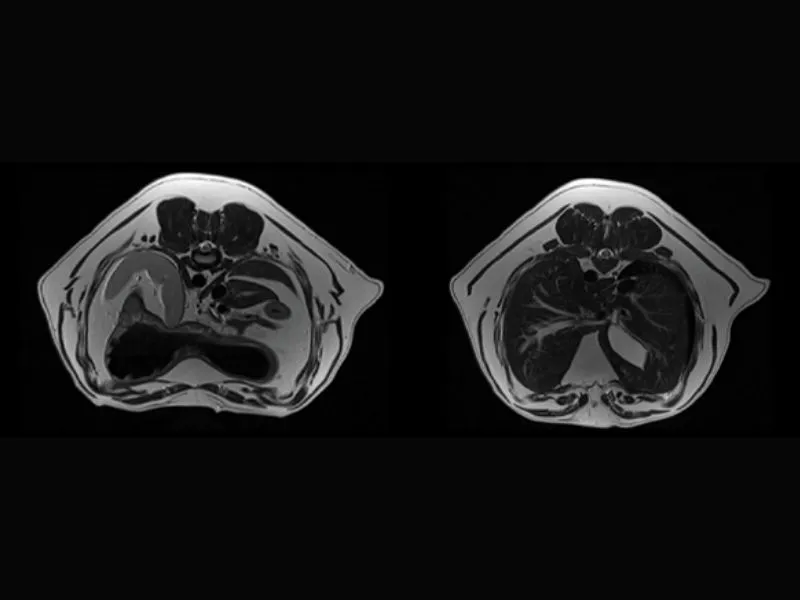

Clinical images

Small animals